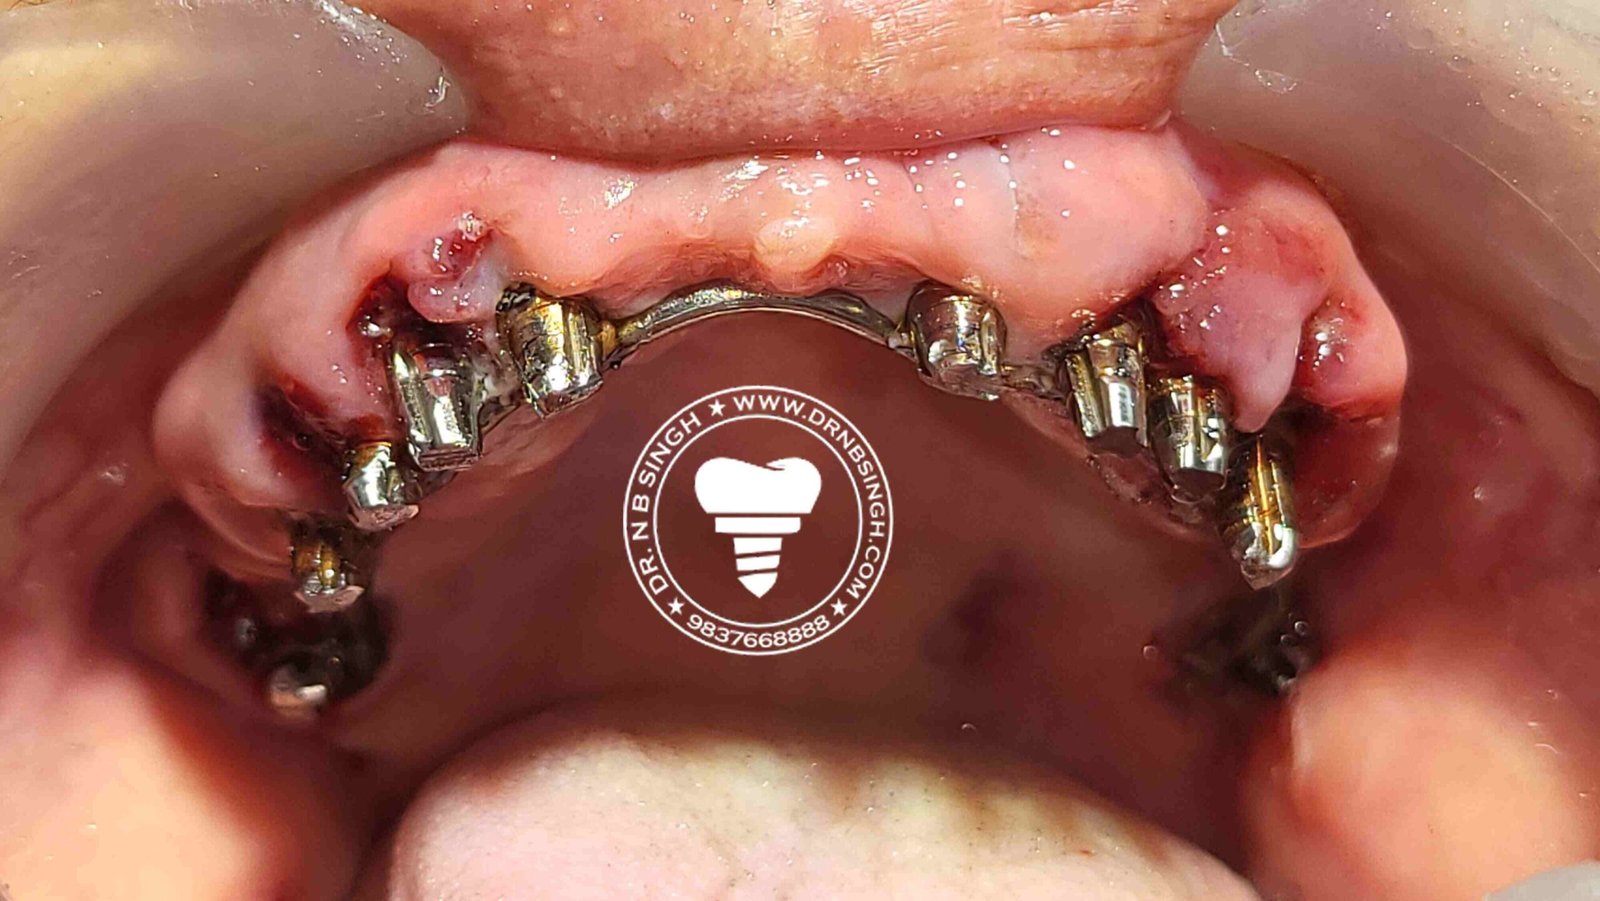

1002 Basal Full Mouth Implants Case Rubeena 2

1002 basal implant full mouth case rub 4